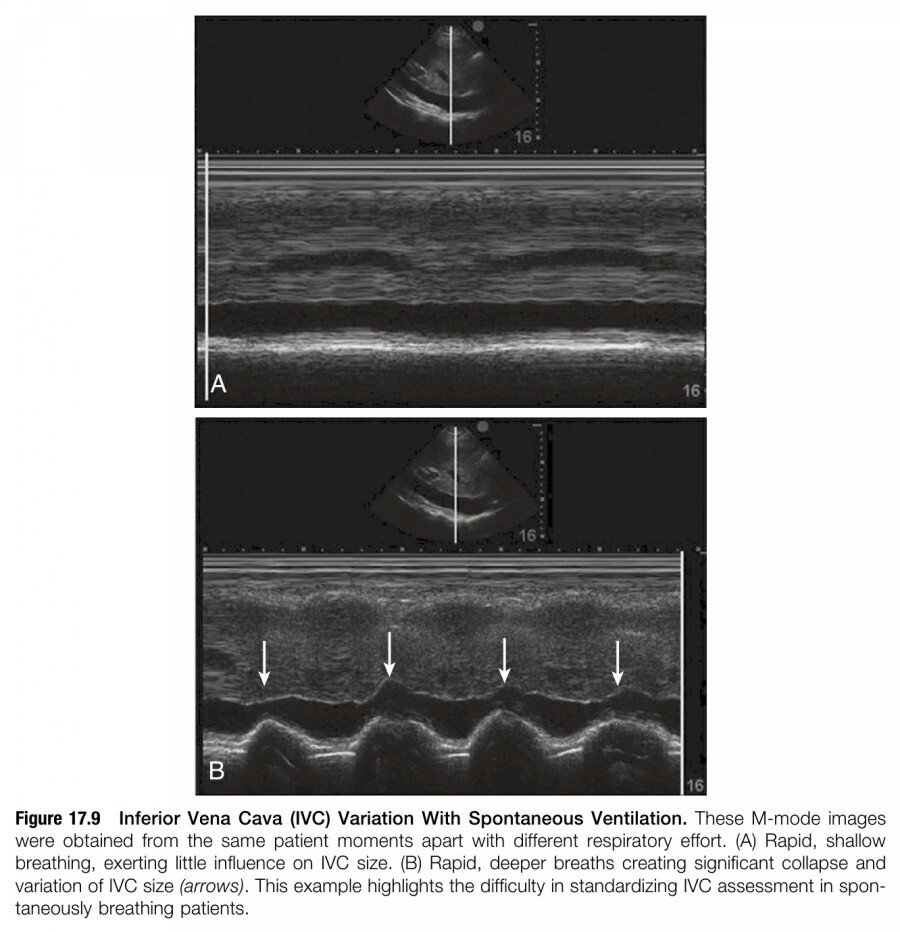

자발 호흡을 하는 환자에서 preload responsiveness 평가를 위해 IVC를 측정하는 것은 상당한 불확실성이 있다. 여러 소규모 연구들에서 IVC index(Diametermax - Diametermin/Diametermax), IVCmax diameter, IVCmin diameter 측정은 비록 modesty accuracy 정도이지만 fluid resposive 한 지 여부를 평가하는데 이용할 수 있다고 보고하였다. 하지만 다수의 연구들은 IVC diameter의 variation과 fluid reponsiveness 사이에 상관관계가 없으므로, 자발 호흡을 하는 환자에게는 단독으로 이용할 수 없다고 하였다(figure 17.9).

Cardiac output 증가를 위해 fluid bolus 투여할지 여부를 결정하는 데 있어서, IVC ultrasound로 측정한 percentage collapse의 cut-off value에 대한 consensus가 현재로서는 없다. 역으로 많은 expert들은 극도로 IVC diameter가 변화한다면 이것만으로도 치료를 guide 하는데 유용하다고 믿고 있다; 하지만 cardiac output에 영향을 미치는 variable들의 heterogeneity로 인해서 앞으로 이에 대한 high quality research가 필요할 것이다. Shock states에서 near-total collapsibility나 small IVC size(<1 cm)은 preload sesitivity를 암시하지만, 다른 임상 data와 heart와 lung의 ultrasound 소견도 함께 종합해서 판단해야 할 것이다.